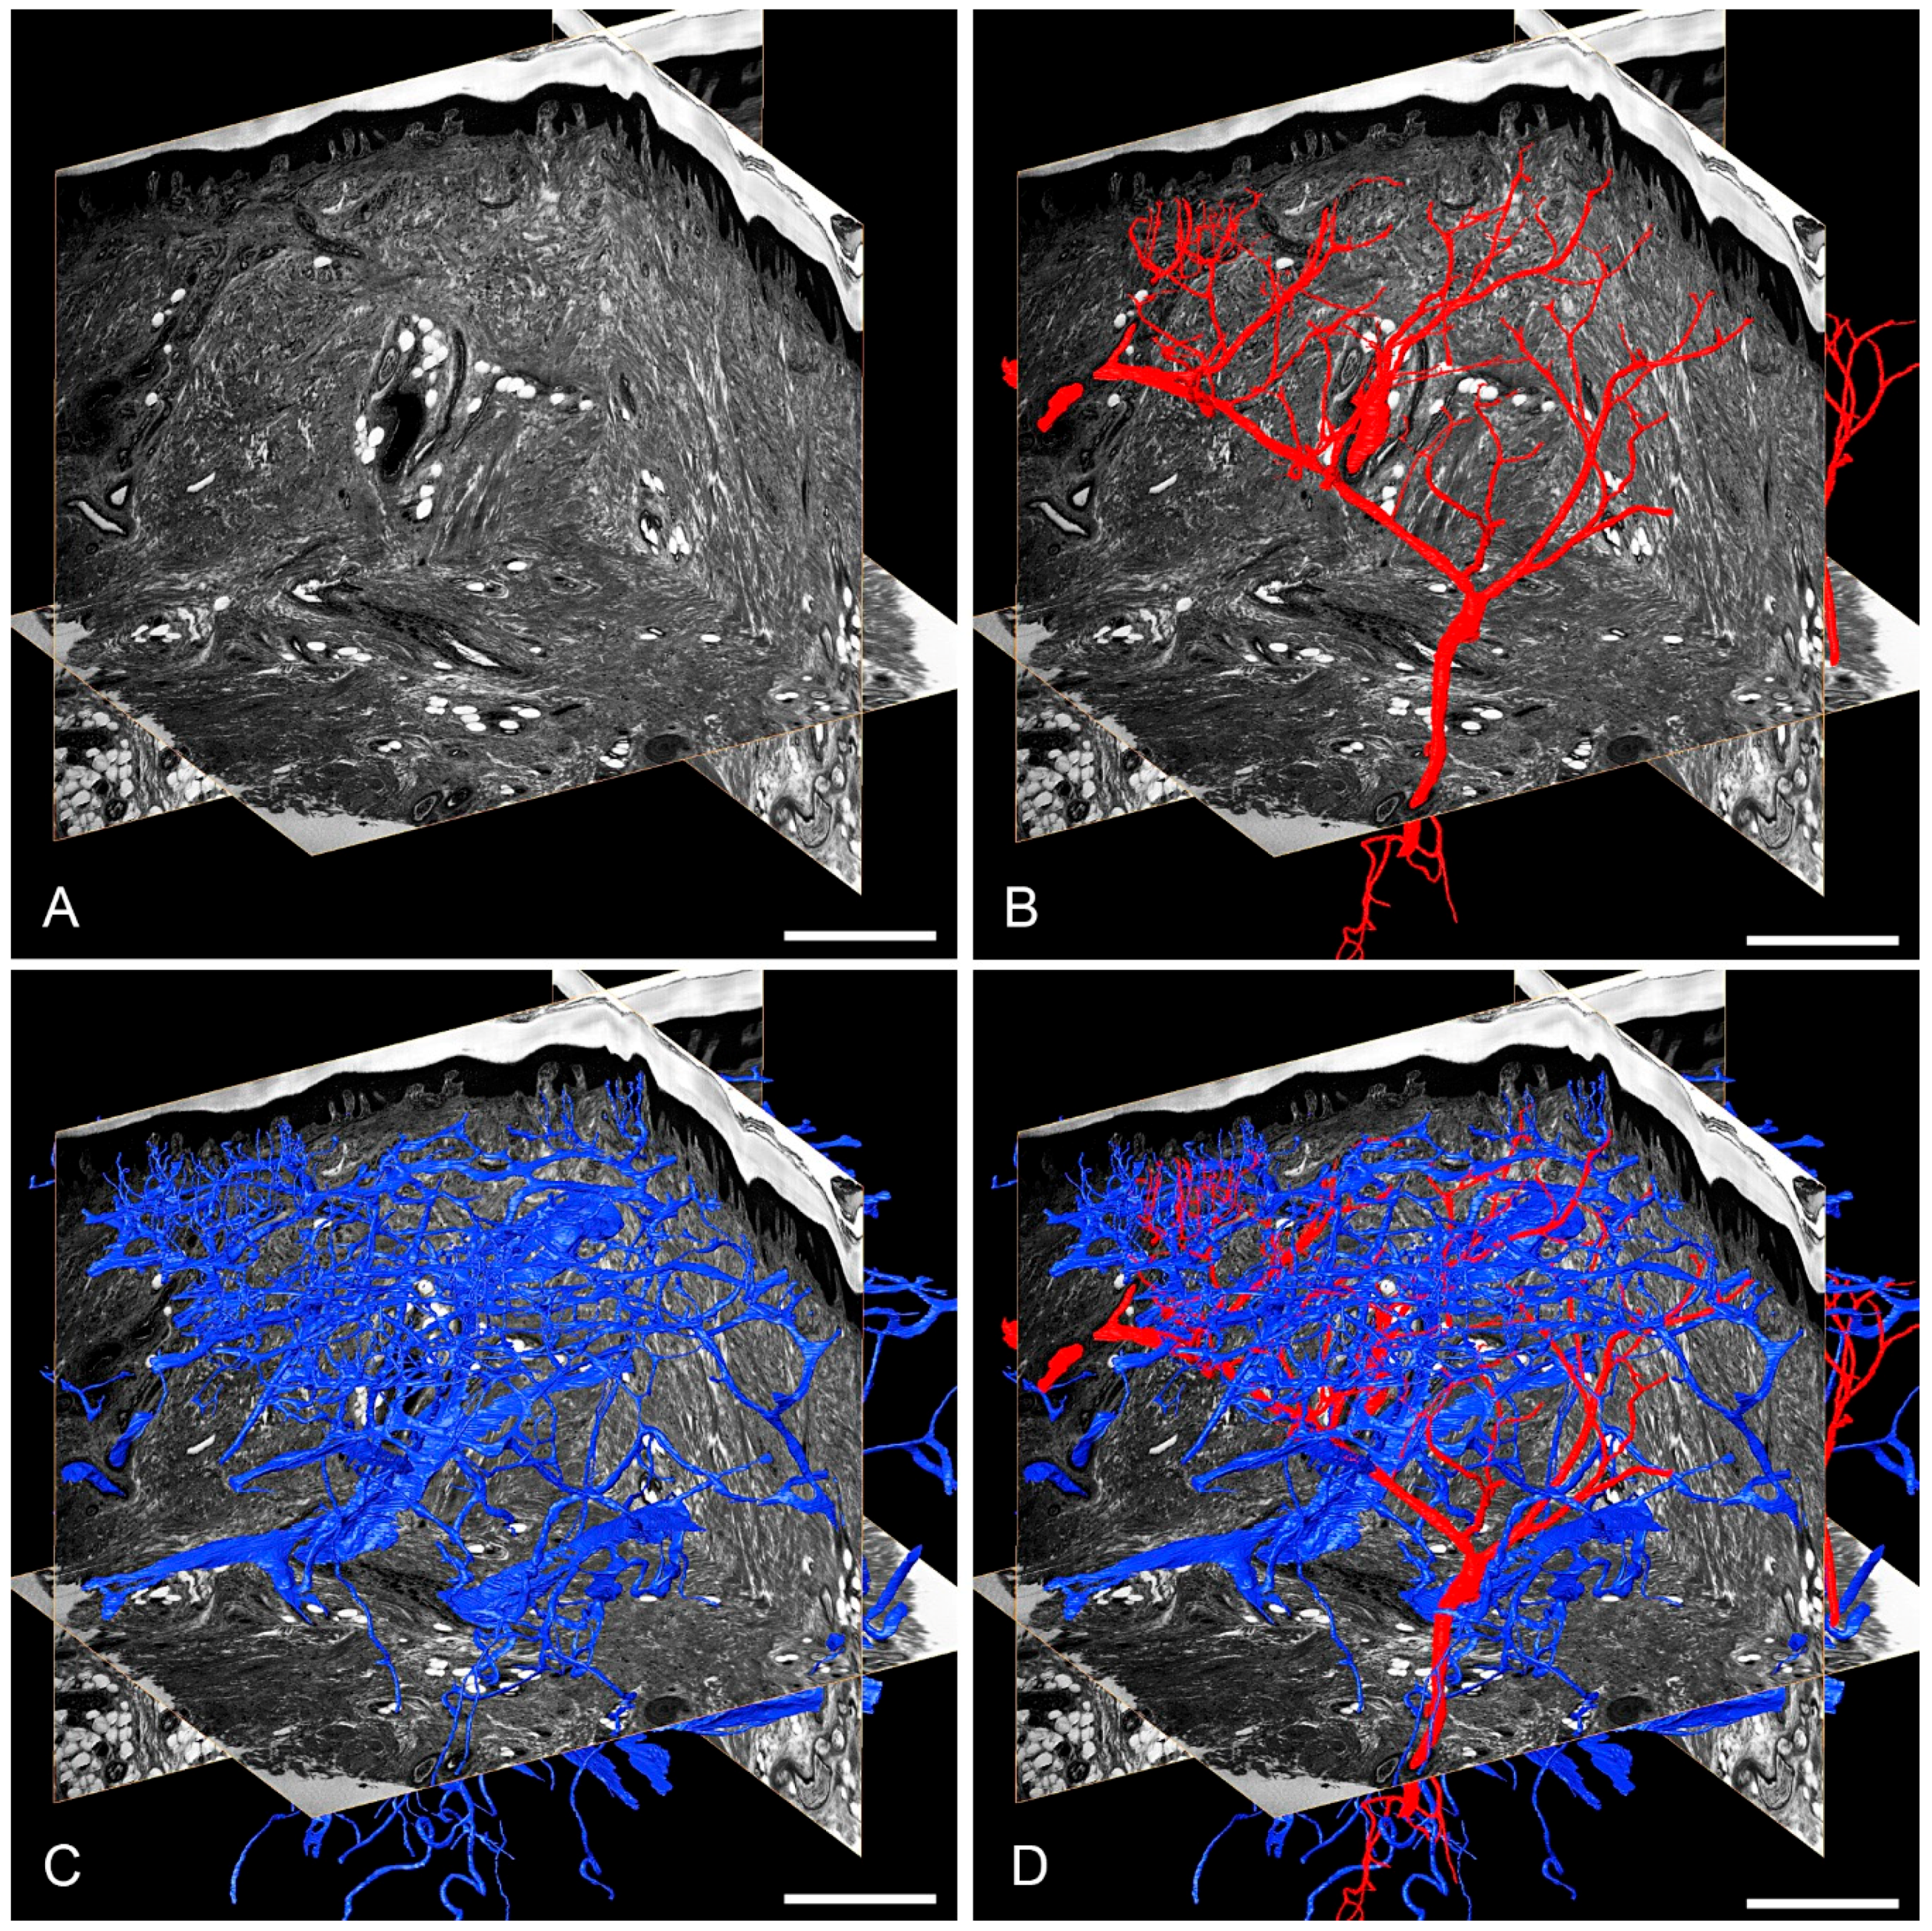

3.1. Skin Vasculature

- Geyer, S.H.; Nöhammer, M.M.; Mathä, M.; Reissig, L.; Tinhofer, I.E.; Weninger, W.J. High-Resolution Episcopic Microscopy (HREM): A Tool for Visualizing Skin Biopsies. Microsc. Microanal. 2014, 20, 1356–1364. [Google Scholar] [CrossRef] [PubMed]

- Geyer, S.H.; Nohammer, M.M.; Tinhofer, I.E.; Weninger, W.J. The dermal arteries of the human thumb pad. J. Anat. 2013, 223, 603–609. [Google Scholar] [CrossRef] [PubMed] [Green Version]

- Tinhofer, I.E.; Zaussinger, M.; Geyer, S.H.; Meng, S.; Kamolz, L.P.; Tzou, C.H.; Weninger, W.J. The dermal arteries in the cutaneous angiosome of the descending genicular artery. J. Anat. 2018. [Google Scholar] [CrossRef]

- Geyer, S.H.; Tinhofer, I.E.; Lumenta, D.B.; Kamolz, L.P.; Branski, L.; Finnerty, C.C.; Herndon, D.N.; Weninger, W.J. High-resolution episcopic microscopy (HREM): A useful technique for research in wound care. Ann. Anat. 2015, 197, 3–10. [Google Scholar] [CrossRef]